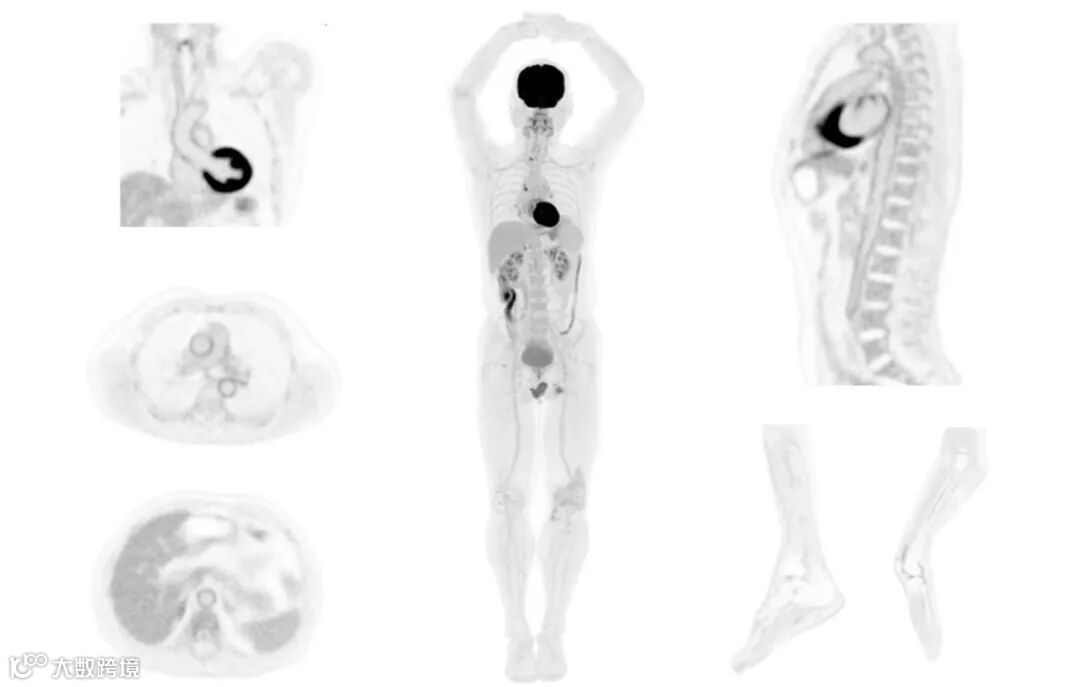

同機器uEXPLORERは米国のPET研究開発コンソーシアムEXPLORERと共同開発したもの。194cmの体軸方向視野を持ち、静止画・動画の両方で全身のスキャン画像を撮影できる。解像度は2.9mm。従来のPMTシステムに比べ30~40倍の高感度を持つため、より低放射性の薬剤の使用と長時間経過後の高精度映像の確保が可能となる。全身の撮像所要時間は1分以内。患者の負担を抑制するとともに、身動きに伴う画像の乱れを減少させ診断精度の向上を図る。

↑ 7.8mCiの薬剤を注射して14分経過後の全身画像(United Imagingのニュースリリースより)